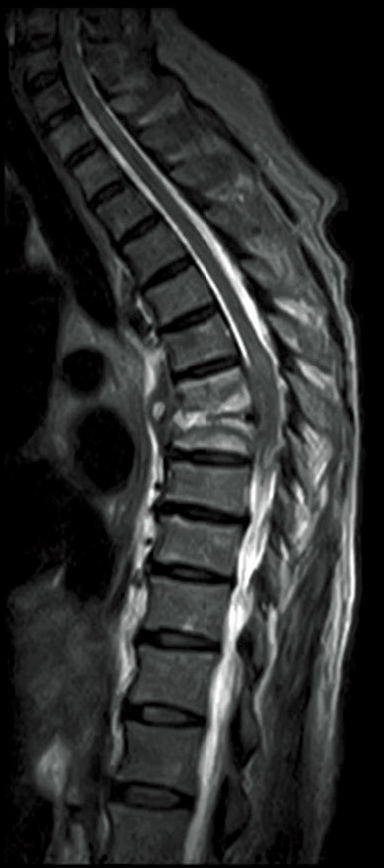

T2WI